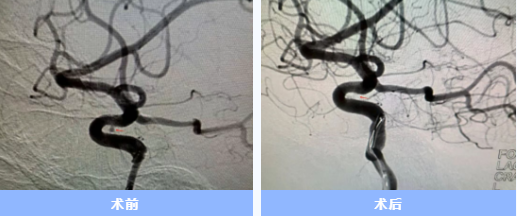

人的大腦里,有時(shí)候血管會(huì)悄悄鼓起一個(gè)“小泡”,它就像一顆“不定時(shí)炸彈”,一旦破裂就會(huì)危及生命。近日,隨州市中心醫(yī)院神經(jīng)內(nèi)科團(tuán)隊(duì)成功通過手腕橈動(dòng)脈穿刺入路,為6位顱內(nèi)動(dòng)脈瘤患者完成介入栓塞手術(shù)。6位患者均已轉(zhuǎn)危為安,其中3人康復(fù)出院,3人在院恢復(fù)中。

手術(shù)當(dāng)天,胡蘇華與主治醫(yī)師陳浩協(xié)作,首先經(jīng)患者右手橈動(dòng)脈成功建立治療通道,隨后才實(shí)施全身麻醉,以最大限度縮短麻醉時(shí)間。憑借精湛技藝,團(tuán)隊(duì)迅速而完整地栓塞了動(dòng)脈瘤。術(shù)后患者很快在ICU蘇醒,四肢活動(dòng)良好,第二天即返回普通病房。

顱內(nèi)動(dòng)脈瘤就像是埋在顱內(nèi)的"不定時(shí)炸彈",傳統(tǒng)手術(shù)需從大腿股動(dòng)脈穿刺,術(shù)后患者需平臥制動(dòng)6-24小時(shí)。而經(jīng)手腕穿刺的介入治療,則大幅提升了患者舒適度——術(shù)后不需長時(shí)間臥床,可早期下地活動(dòng),恢復(fù)體驗(yàn)明顯改善。

隨州市中心醫(yī)院神經(jīng)內(nèi)科自2016年起獨(dú)立開展顱內(nèi)動(dòng)脈瘤介入手術(shù),至今已有近十年經(jīng)驗(yàn),每年完成動(dòng)脈瘤介入手術(shù)一百余例。此次在前期開展經(jīng)橈腦動(dòng)脈造影及缺血性腦血管病治療的基礎(chǔ)上,常規(guī)開展經(jīng)橈治療顱內(nèi)動(dòng)脈瘤,標(biāo)志著該院神經(jīng)介入真正實(shí)現(xiàn)"不僅微創(chuàng),更加舒適"。 (供稿通訊員:陳浩)